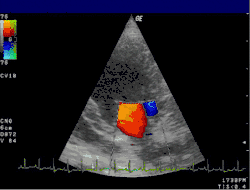

Цветовое доплеровское картирование (ЦДК)

При этом методе в цвете кодируется не средняя величина доплеровского сдвига, как при обычном доплеровском картировании, а интеграл амплитуд всех эхосигналов доплеровского спектра. Это даёт возможность получать изображение кровеносного сосуда на значительно большем протяжении, показывать сосуды даже очень небольшого диаметра (ультразвуковая ангиография). На ангиограммах, полученных с помощью энергетического доплера, отражается не скорость движения эритроцитов, как при обычном цветовом картировании, а плотность эритроцитов в заданном объёме. Благодаря своим диагностическим возможностям, ультразвуковая ангиография методом энергетического доплера в ряде случаев может заменить более инвазивную рентгеновскую ангиографию.